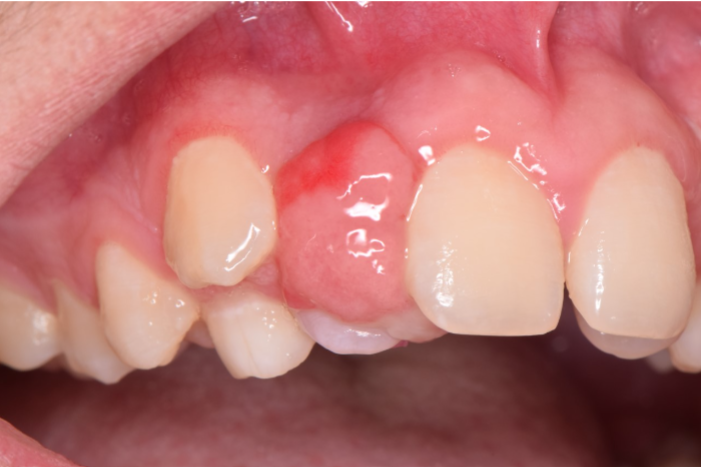

Oral Pathology Case 1 (Photo credit Dr. Marcos Garcia)

What is the MOST likely diagnosis for this lesion?

Answer: D. Peripheral ossifying fibroma

This month’s case features a bump on the gum. The main differential diagnosis for these lesions include pyogenic granuloma, peripheral giant cell granuloma, and peripheral ossifying fibroma.

The main entities in the differential diagnosis are all reactive lesions rather than true neoplasms. They represent a growth on the gingiva occurring in response to something such as calculus build up. In pathology, the word ‘peripheral’ means ‘on the gingivae’ – therefore, the only place one can encounter a peripheral ossifying fibroma or peripheral giant cell granuloma is the gingiva. Though 75% of pyogenic granulomas occur on the gingivae, they can also occur anywhere in the oral cavity. Pyogenic granulomas are also known as “pregnancy tumors” as they occur with higher frequency in pregnant women, though men and non-pregnant women can also get pyogenic granulomas.

The best treatment for these lesions is surgical excision with submission for histologic evaluation. This is the treatment for a couple of reasons – first, the lesions will not go away without a biopsy. Second, we do need to rule out the rare cases of malignancy presenting as reactive bumps on the gum. Inform the patient that all three have about a 10-15% recurrence rate.